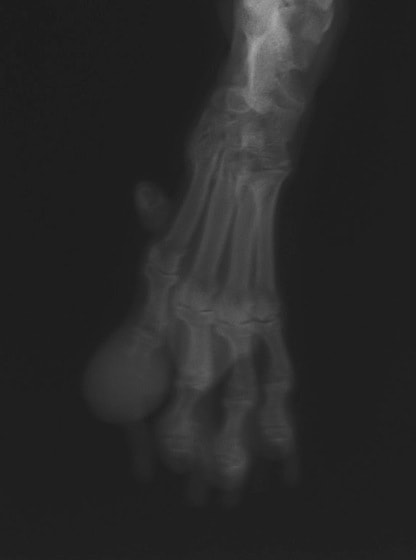

レントゲン検査

レントゲン検査所見から、骨もしくはその周囲組織に発生した腫瘍の可能性が考えられたため、病変部の細胞診検査およびジャムシディ生検針を用いた病変の骨生検を実施した。病理組織検査の結果、非上皮性の悪性腫瘍である“肉腫”と診断された。

内科治療に反応が乏しい四肢の跛行や疼痛は、本症例のように腫瘍が原因となっていることがあるため、レントゲン検査、骨生検等積極的に原因追及のための検査を実施することが必要である。骨の破壊を起こす悪性腫瘍は、非常に強い痛みを伴い、消炎鎮痛剤を用いても痛みを抑えることが困難となる。痛みの除去および腫瘍の治療のために断脚手術や抗がん剤等が必要となる場合があり、似た症状を示す整形外科疾患等とは治療法・予後が異なるため、その鑑別は重要である。